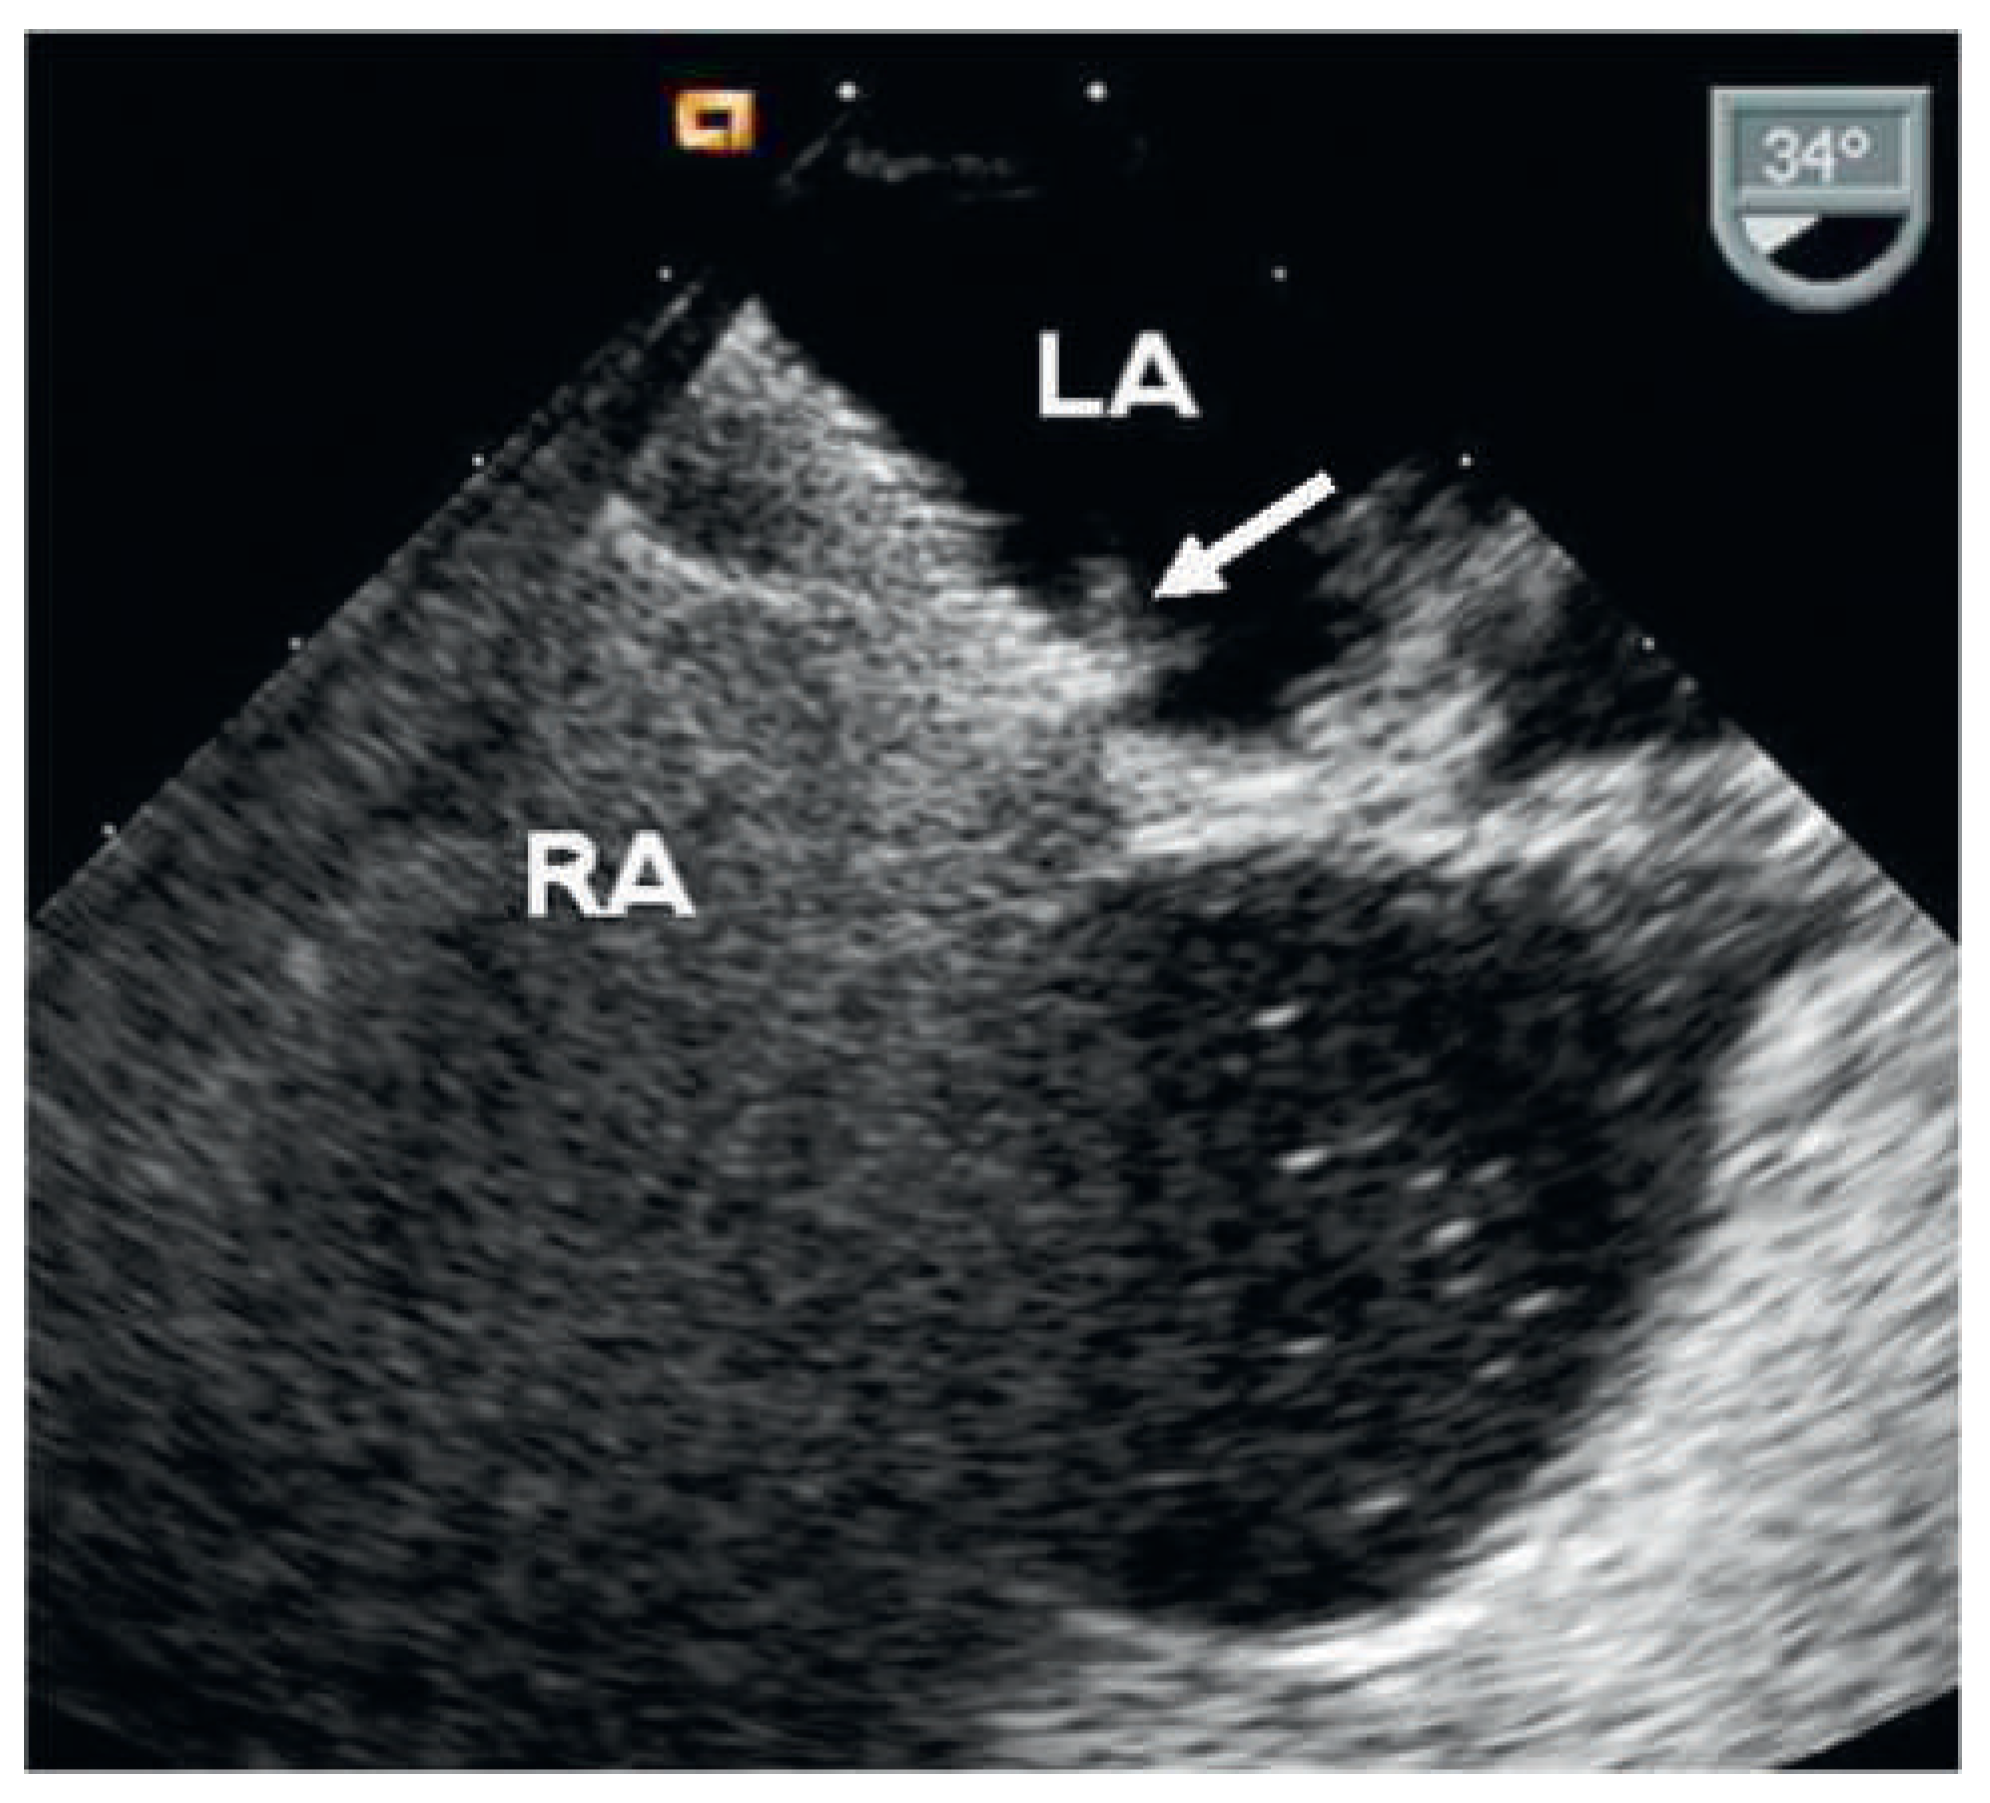

Figure 4. Contrast TEE 6 months after implantation of the second device with residual shunt grade 2 (arrow). LA = left atrium; RA = right atrium.

Six months after implantation of the second device, contrast TOE revealed correct position of both devices but a persisting shunt grade II (Figure 4). A third APFO (18-mm) was implanted using the same technique (Figure 5). Contrast TTE at discharge the same day assessed good position of the device without any residual shunt. Clopidogrel 75 mg was again prescribed for 1 month and acetylsalicylic acid 100 mg for 5 months. Six months after implantation of the third device, contrast TOE finally showed complete occlusion (Figure 6) and both platelet inhibitors were stopped.